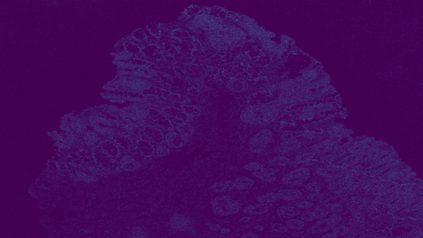

The usage of chemical imaging technologies is becoming a routine accompaniment to traditional methods in pathology. Significant technological advances have developed these next generation techniques to provide rich, spatially resolved, multidimensional chemical images. The rise of digital pathology has significantly enhanced the synergy of these imaging modalities with optical microscopy and immunohistochemistry, enhancing our understanding of the biological mechanisms and progression of diseases. Techniques such as imaging mass cytometry provide labelled multidimensional (multiplex) images of specific components used in conjunction with digital pathology techniques. These powerful techniques generate a wealth of high dimensional data that create significant challenges in data analysis. Unsupervised methods such as clustering are an attractive way to analyse these data, however, they require the selection of parameters such as the number of clusters. Here we propose a methodology to estimate the number of clusters in an automatic data-driven manner using a deep sparse autoencoder to embed the data into a lower dimensional space. We compute the density of regions in the embedded space, the majority of which are empty, enabling the high density regions to be detected as outliers and provide an estimate for the number of clusters. This framework provides a fully unsupervised and data-driven method to analyse multidimensional data. In this work we demonstrate our method using 45 multiplex imaging mass cytometry datasets. Moreover, our model is trained using only one of the datasets and the learned embedding is applied to the remaining 44 images providing an efficient process for data analysis. Finally, we demonstrate the high computational efficiency of our method which is two orders of magnitude faster than estimating via computing the sum squared distances as a function of cluster number.